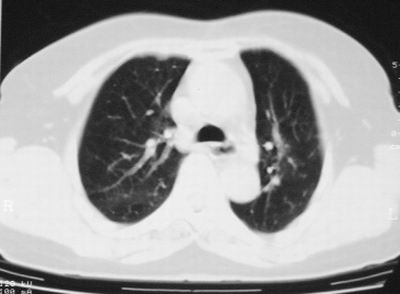

患者,女,64岁,4年前左腮腺"多形性"腺瘤手术治疗史.现复查胸部ct见左下肺块状影,该影与原左腮腺手术是否有联系?

本次复查胸部ct

左下肺软组织块影,有分叶、毛刺、空泡及胸膜牵拉征,左下肺周围性肺癌。

左肺下叶周围型肺癌,支持!(软组织肿块+分叶+毛刺+空泡+胸膜凹陷征)

左下肺软组织密度影,可见分叶,边缘可见毛刺征,胸膜增厚,强烈要求左下肺周围型肺癌

左下肺后基底段实性肿块,周围有毛刺,病变周围有肺气肿,与降主动脉间有条带状影相连,病灶4年前查体发现,纵隔内未见肿大淋巴结。考虑.肺隔离症,建议增强扫描与周围型肺癌鉴别。